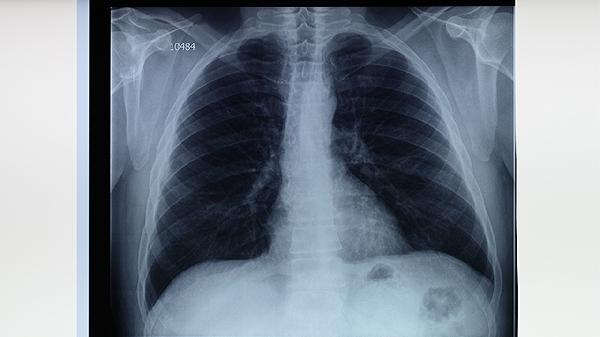

如果双腿出现上述异常,特别是同时有咳嗽、消瘦等症状,建议尽快做低剂量螺旋CT检查。记住:肺癌不是突然发生的,只是信号太容易被忽略。现在就去观察一下自己的双腿,它们可能正在为你敲响健康的警.钟!